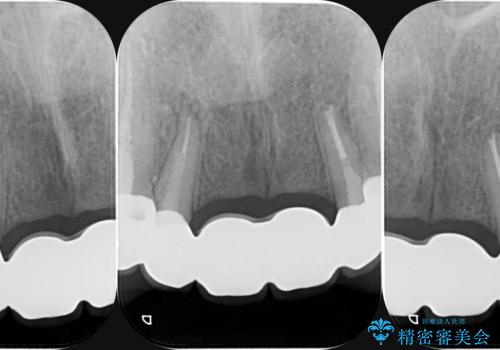

- 数ヶ月前に治療終了したブリッジの歯ぐきの違和感が強く、改善を求めて来院されました。

歯ぐきは著しく腫れ、少し触ると出血してしまうような状態であったためブリッジの再作製・歯周外科を用いた歯肉環境の改善を計画します。